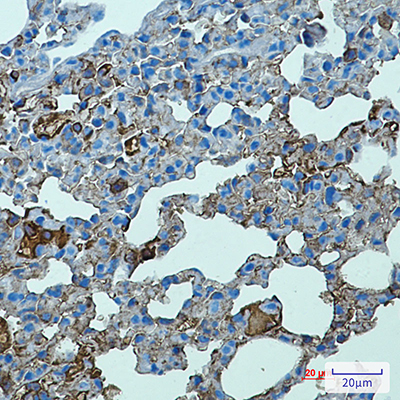

WB,IHC-F,IHC-P,ICC/IF

稀释比(Dilution Ratio)

WB: 1:500-1:1000 IHC: 1:50-1:100 IF: 1:50-1:200